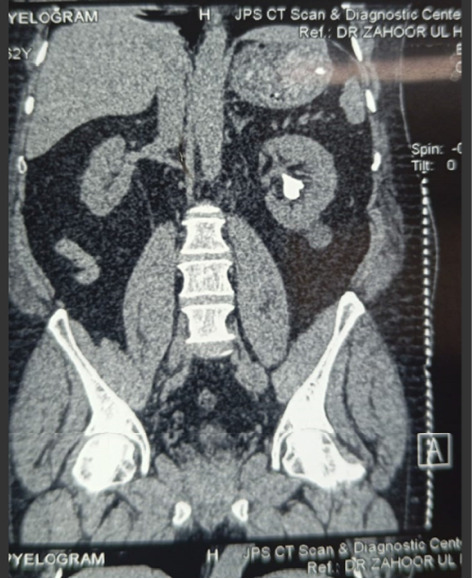

Background: After percutaneous nephrolithotomy (PCNL), intravenous misplacement of a nephrostomy tube is a very rare clinical occurrence. This report summarizes the characteristics and management of intravenous misplacement of a nephrostomy tube. Case Presentation: We present a rare case of intravenous nephrostomy catheter misplacement after PCNL in a 63 years old male. The tip of the tube was located in the left renal vein. The patient was managed conservatively and treated safely. Conclusion: Intravenous nephrostomy tube misplacement is a rare PCNL complication. Good Imaging can rule out through and through renal vein perforation and thus patients can be safely managed using conservative approach.

Abstract Image